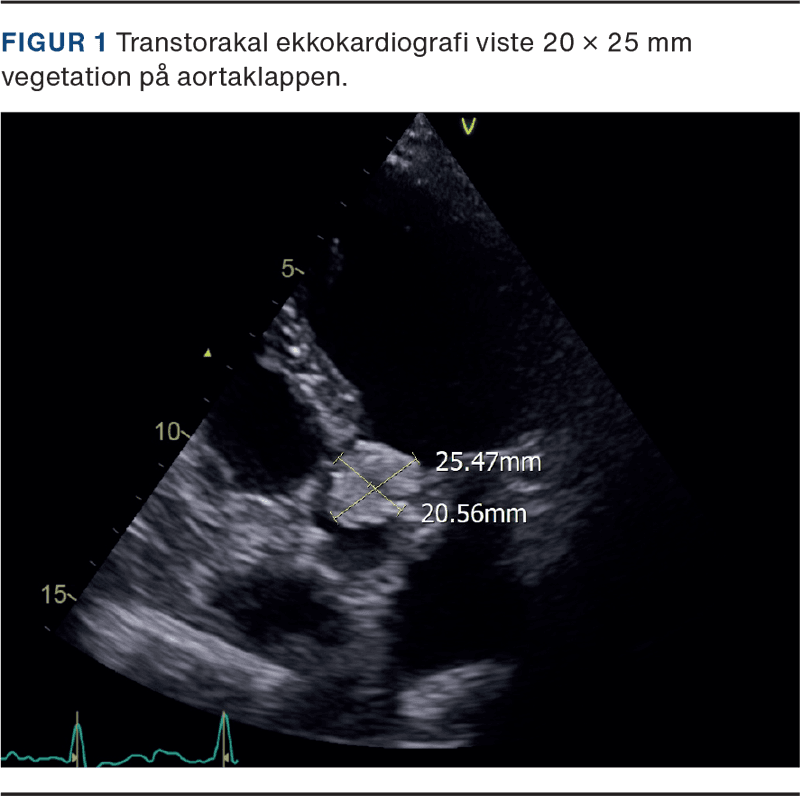

To måneder senere blev patienten genindlagt grundet cikatricedefekt. Patienten var siden ileusoperationen blevet rollatorbruger og havde kronisk diarré. Ved eksplorativ laparotomi blev der vurderet pæne forhold intraabdominalt. Der blev foretaget bloddyrkning × 2, som tilsvarende to måneder tidligere påviste C. glabrata i to ud af to kolber, og der var intet resistenssvar. Klinisk observeredes et blodtryk på 91/58 mmHg, sinustakykardi, takypnø med behov for 4 l nasalt ilttilskud og tiltagende konfusion. Patienten var ydermere sengeliggende. En CT af thorax blev beskrevet med bilateral bronkopneumoni og bilateral pleuraeffusion. Ved en transtorakal ekkokardiografi (TTE) blev der fundet en 20 × 25 mm stor, mobil vegetation på aortaklappen (Figur 1), moderat obstruktion, gradient over aortaklappen på 54 mmHg, let aortainsufficiens uden større klapdestruktion og venstre ventrikel ejection fraction på 60%. Patienten diagnosticeredes således med C. glabrata-endokarditis. Der blev afstået fra transøsofagal ekkokardiografi, da diagnosen var sikker ud fra TTE. I samråd med Rigshospitalet blev det vurderet, at kirurgisk behandling ikke var udelukket, men at der forventedes et langvarigt, kompliceret forløb med høj mortalitetsrisiko. På baggrund af den medtagne kliniske tilstand og samtidig pneumoni blev det besluttet i første omgang at tillægge antifungal behandling med i.v. echinocandin og forsøge at optimere tilstanden inden senere revurdering af, om patienten skulle flyves til Rigshospitalet til kirurgisk behandling. I løbet af de kommende to døgn blev patienten ukontaktbar og døde kort inden, den antifungale behandling ankom til Grønland.